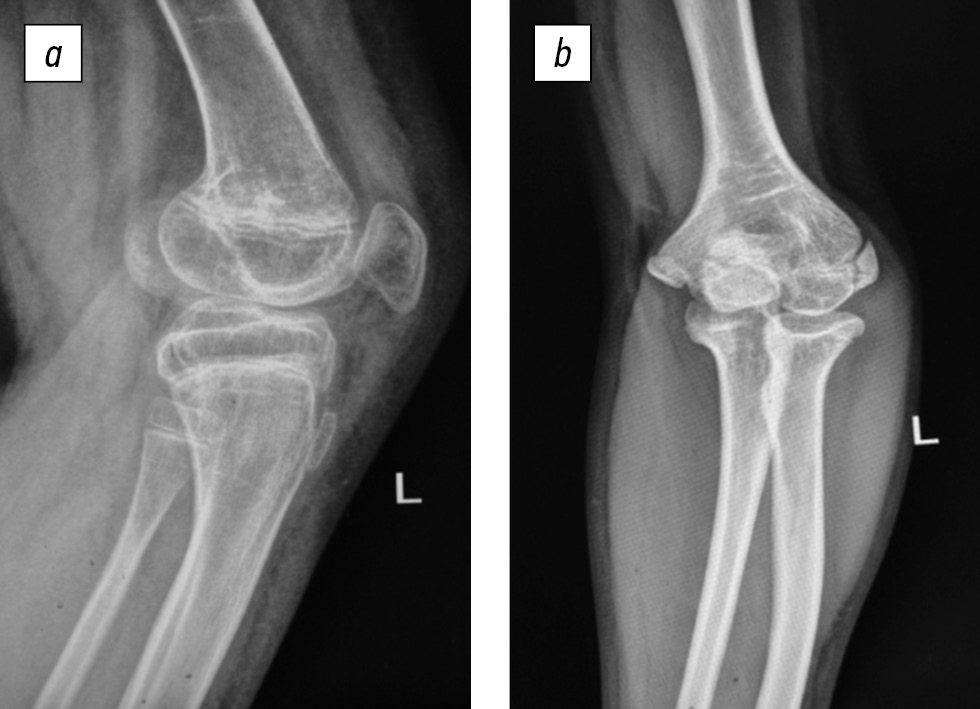

Concurrently, other anatomical and functional disorders of the affected limb segments appeared in the growth process, namely, left femur shortening and left femur and tibia antecurvation deformity, which imitates knee joint flexion contracture, as well as left elbow joint varus deformity (2020) (Fig. 3).

Fig. 3. Left knee (a) and elbow (b) joint deformities at the treatment stage